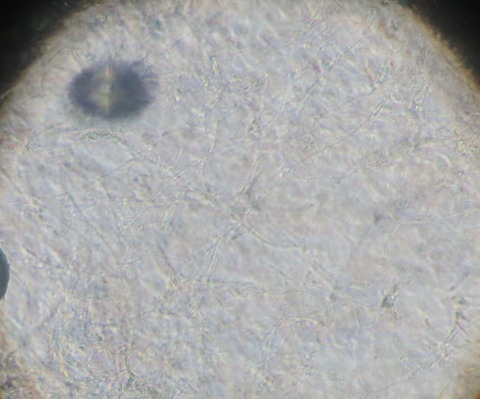

写真の様に皮膚が壊れて深い部分まで損傷している場合に用います。

肉芽や上皮の再生を促してくれる外用薬です。